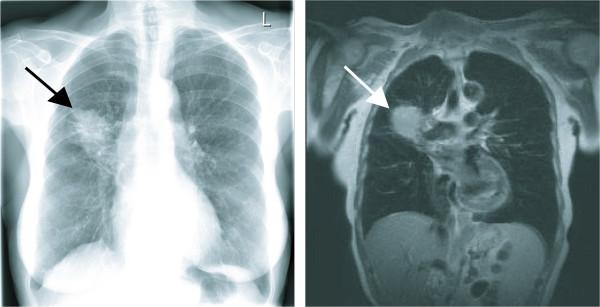

To date, vaccines were successfully manufactured for 4 of 4 patients. The most common toxicities were local injection-site reactions and mild constitutional symptoms. Immune responses to chemotherapy, reconstitution and vaccination are measured by vaccine site and delayed type hypersensitivity (DTH) skin reactions. One patient developed positive DTH skin tests so far. Immunohistochemical assessment of punch biopsies taken at the local vaccine site reaction revealed a dense lymphocyte infiltrate. Further immunohistochemical differentiation showed that CD1a+ cells had been attracted to the vaccine site as well as predominantly CD4+ lymphocytes. The 3-day combination chemotherapy consisting of cyclophosphamide and fludarabine induced a profound lymphopenia in all patients. Sequential FACS analysis revealed that different T cell subsets (CD4, CD8, CD4CD25) as well as granulocytes, B cells and NK cells were significantly reduced. Here, we report on clinical safety and feasibility of this vaccination approach during lymphoid recovery and demonstrate a patient example.

迄今为止,4例患者中有4例成功制备了疫苗。最常见的毒性反应是局部注射部位反应和轻度全身症状。通过疫苗接种部位和迟发型超敏反应(DTH)皮肤反应来测量对化疗、重建和疫苗接种的免疫反应。到目前为止,有1例患者出现了阳性DTH皮肤试验。对局部疫苗接种部位反应处的打孔活检进行免疫组织化学评估显示有密集的淋巴细胞浸润。进一步的免疫组织化学鉴别表明,CD1a+细胞以及主要是CD4+淋巴细胞被吸引到疫苗接种部位。由环磷酰胺和氟达拉滨组成的3天联合化疗在所有患者中均诱导了严重的淋巴细胞减少。连续的流式细胞术分析显示不同的T细胞亚群(CD4、CD8、CD4CD25)以及粒细胞、B细胞和NK细胞均显著减少。在此,我们报告了这种疫苗接种方法在淋巴细胞恢复期间的临床安全性和可行性,并展示了一个患者实例。